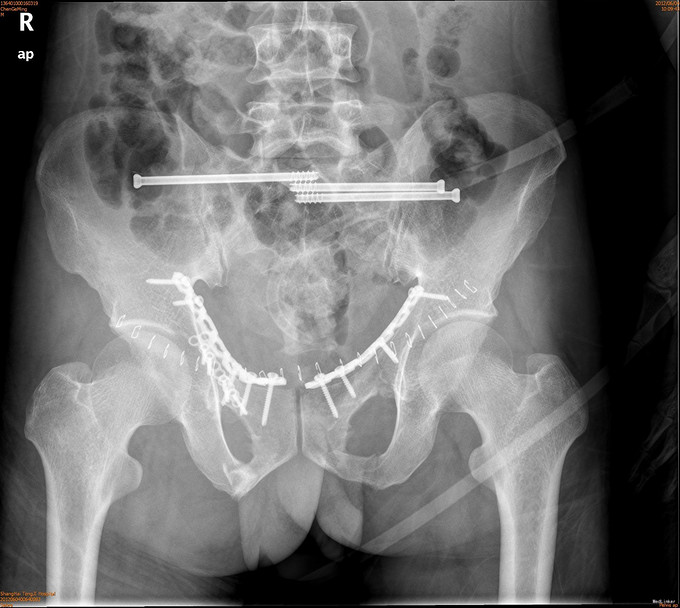

诊断为耻骨上下支骨折,兄弟科室会诊治疗结束后,患者病情稳定,行切开复位内固定术。

1年后随访患者无疼痛,活动可。耻骨上下支骨折ORIF术疗效良好。